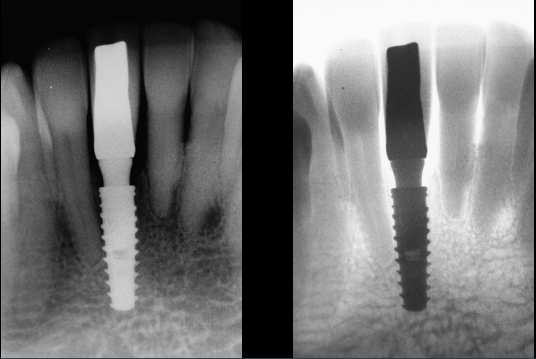

Após 35 dias da instalação do implante foi realizada a abertura do implante através de um bisturi circular e o pilar Ideale reto de 3.3 X 4.0 X 2.5 mm foi torqueado no implante a 20 Ncm. Foi realizada também uma moldagem deste pilar com o seu transferente correspondente e a prótese adesiva voltou a ser instalada. Depois de uma semana, o provisório parafusado confeccionado no laboratório foi instalado e mantido em posição durante 15 dias para formar um novo perfil de emergência, aproximando as características dos tecidos circundantes às características de um incisivo central inferior. Neste momento, foi realizada uma nova moldagem da região e uma coroa metalocerâmica foi confeccionada e instalada após uma semana. Foi também realizada a radiografia.